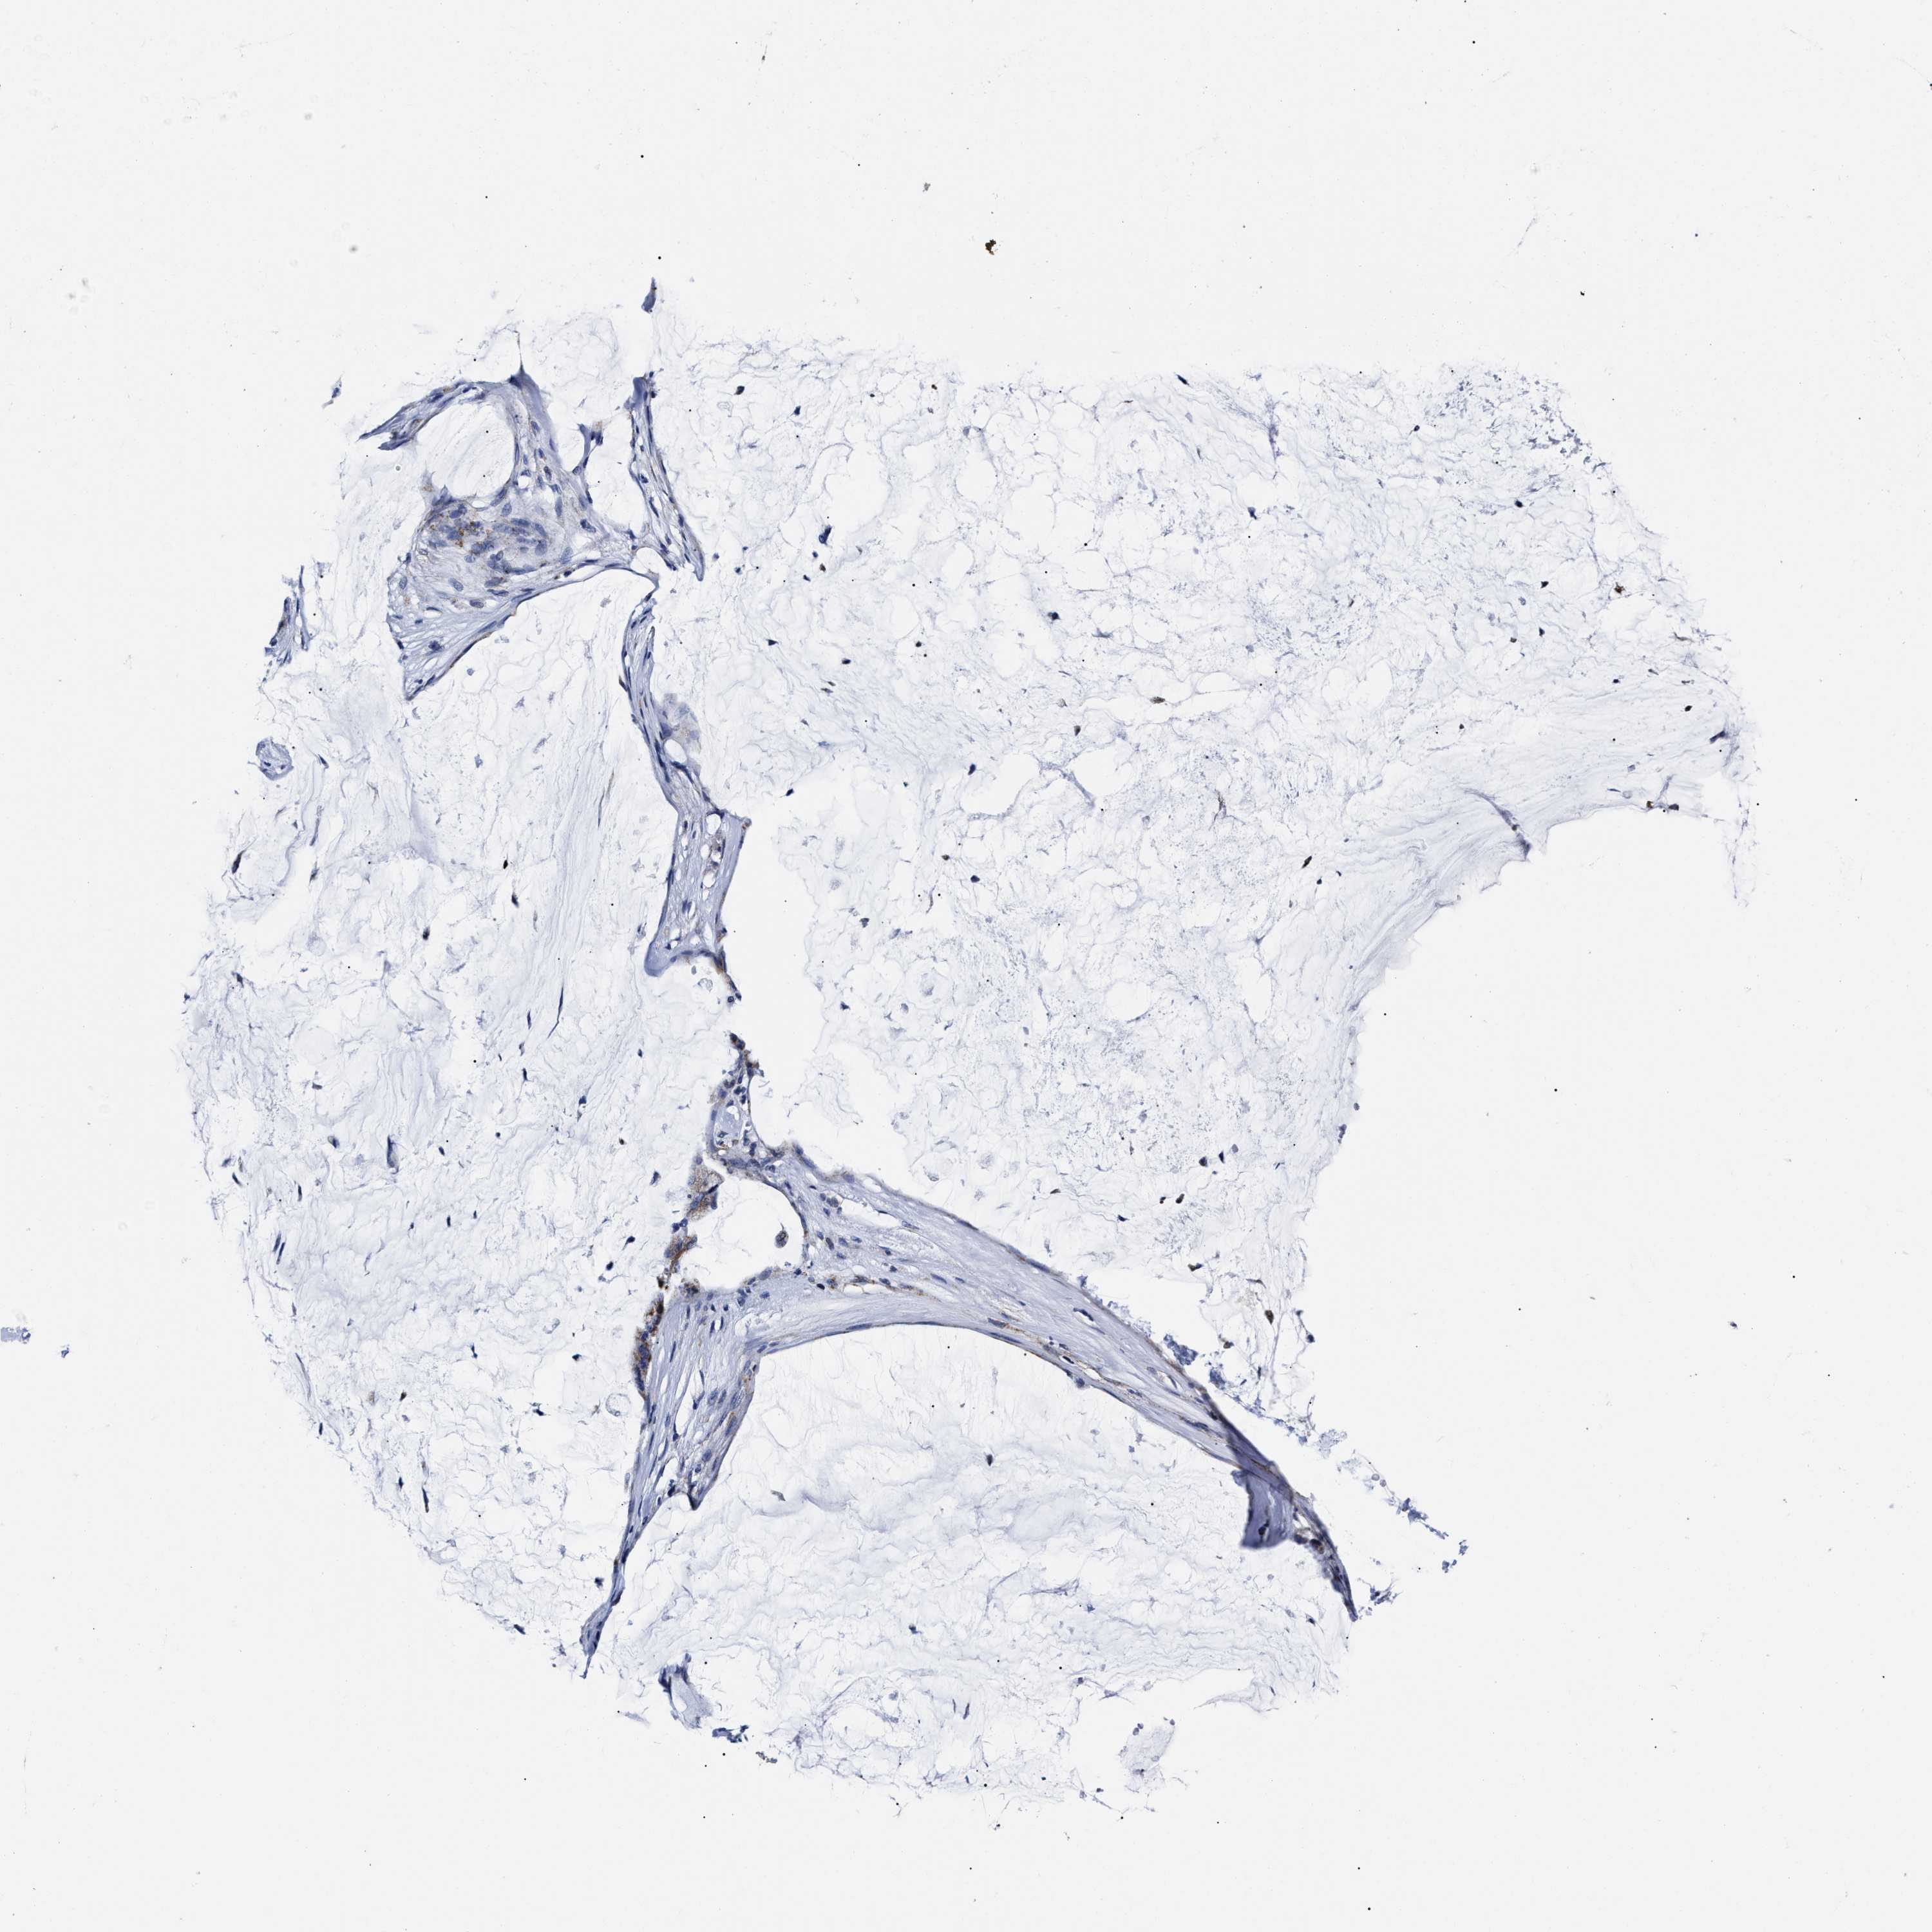

PANCREATIC CANCER - Protein expressioni

A mouse-over function shows sample information and annotation data. Click on an image to view it in a full screen mode. Samples can be filtered based on level of antibody staining by selecting one or several of the following categories: high, medium, low and not detected. The assay and annotation is described here.

Note that samples used for immunohistochemistry by the Human Protein Atlas do not correspond to samples in the TCGA dataset.

Antibody stainingi

Antibody staining in the annotated cell types in the current human tissue is reported as not detected, low, medium, or high, based on conventional immunohistochemistry profiling in selected tissues. This score is based on the combination of the staining intensity and fraction of stained cells.

Each image is clickable and will lead to virtual microscopy that enables deeper exploration of all samples and also displays staining intensity scores, fraction scores and subcellular localization as well as patient and tissue information for each sample.

Antibody HPA020961

Antibody HPA059109

Staining

High

Medium

Low

Not detected

Intensity

Strong

Moderate

Weak

Negative

Quantity

>75%

75%-25%

<25%

None

Location

Nuclear

Cytoplasmic/membranous

Cytoplasmic/membranous,nuclear

Adenocarcinoma, NOS